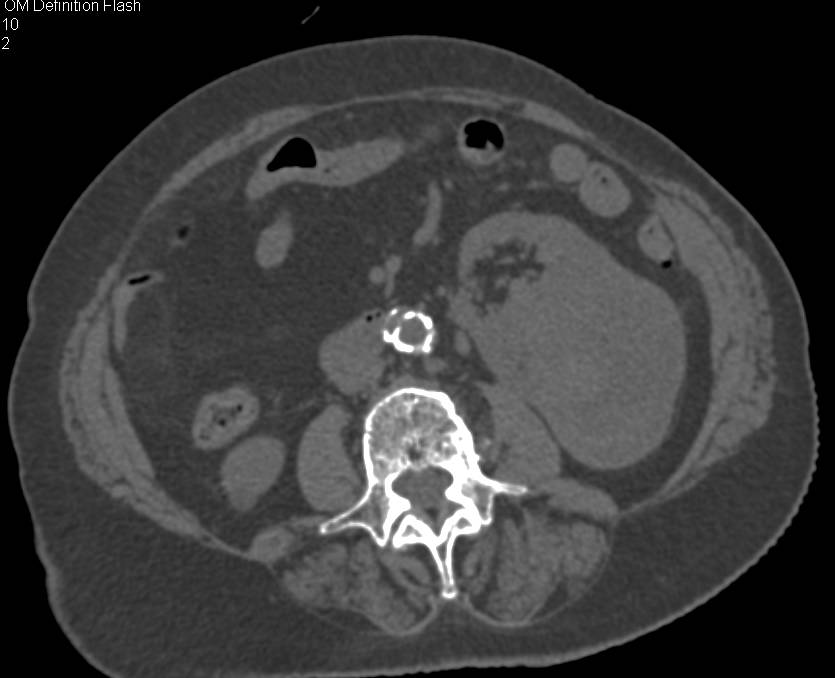

Contrast Injection Timed for Right Side of the Heart and Pulmonary Arteries